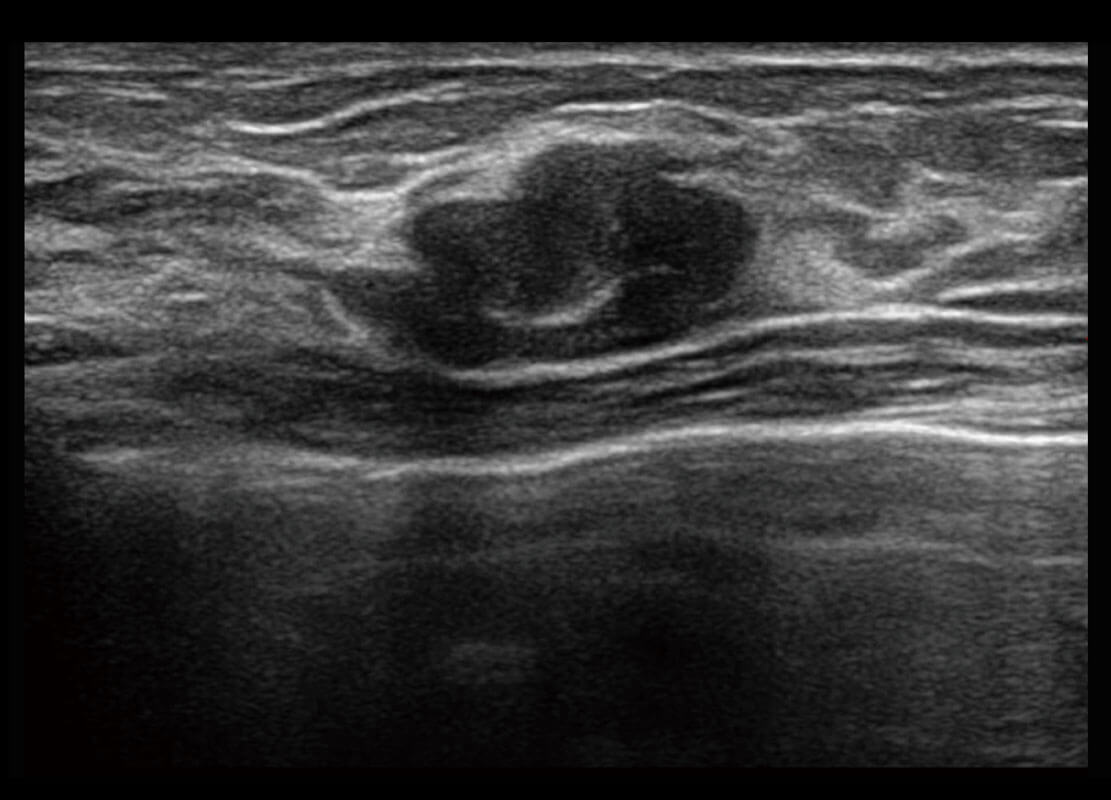

乳腺导管癌

P60搭载宽频带线阵探头、宽景成像、弹性成像技术,为您提供乳腺应用方案。P60支持高频相控阵探头、线阵探头、腹部高频探头、腹部微凸探头等,丰富的探头群搭载敏感的彩色血流成像,适用于新生儿多种脏器检测要求,满足新生儿筛查需求。